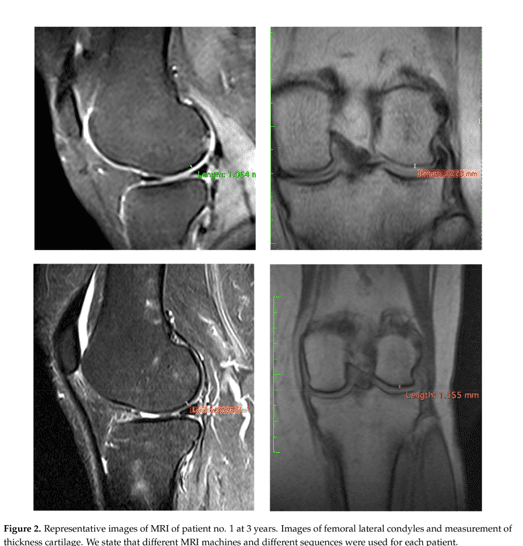

Specialistii dar si pacientii cu “experienta” in artroza, pot identifica castigul de grosime a tesutului articular comparand imaginea de sus cu cea de jos respectiv aceeasi incidenta a articulatiei investigate RMN inainte de administrarea terapiei Rigenera in artroza si apoi la 3 ani dupa tratament.

- Fiecare calup de imagini reprezinta cate un pacient investigat cu incidenta frontala si laterala. Detalii suplimentare in marginea inferioara a fiecarei imagini - interpretarea imaginilor se face pe 1/2 stanga sus versus jos si 1/2 dreapta sus versus jos.